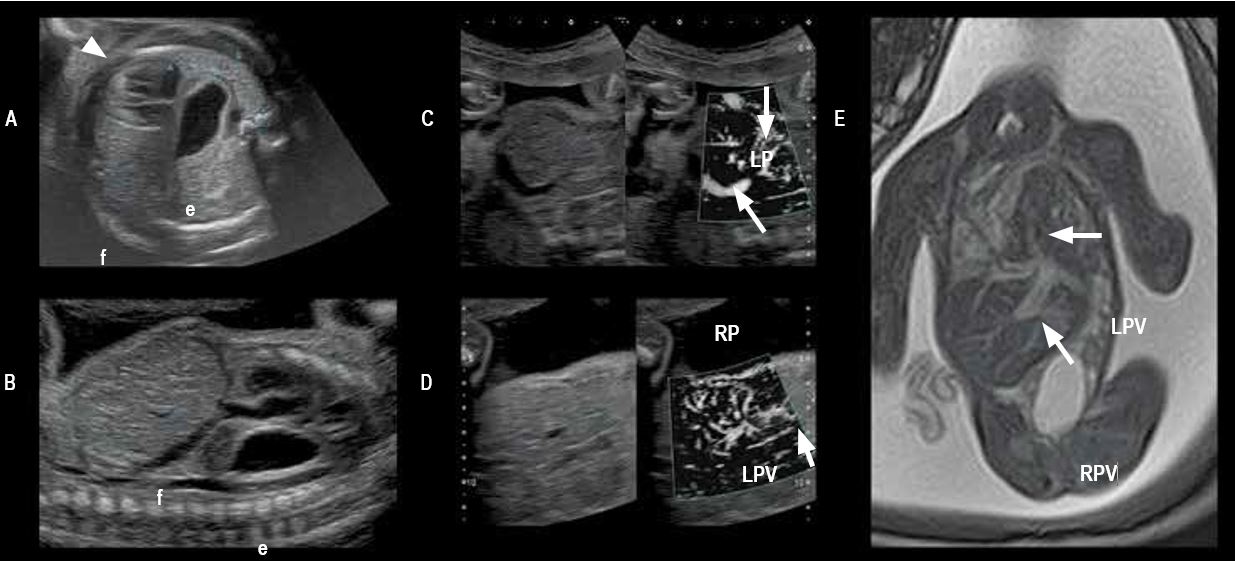

Діафрагмальна грижа (мал. 7)

Вклинювання грижового мішка з частиною печінки в грудну клітину є несприятливим прогностичним фактором при лівій діафрагмальній грижі. Іноді важко диференціювати паренхіму печінки та паренхіму легень до 3-го триместру, оскільки ехогенність печінки та легень однакова.

Аналіз типу гемодинаміки дозволяє виконати їхню ідентифікацію, але чутливості традиційного доплерівського картування іноді буває недостатньо для плоду. Завдяки високій чутливості режиму SMI цю проблему можна вирішити за допомогою візуалізації судинного малюнка печінки.

Мал. 7. Ліва діафрагмальна грижа на 26 тижні вагітності:

A - аксіальний зріз грудної клітки на рівні серця (стрілка) зі зміщенням вправо, шлунок (e) перед хребтом плода, зліва переднебокова маса – як передбачається - печінка (f);

B - правий парамедіальний поздовжній зріз, на якому печінка (f) розташована інтраабдомінально, а шлунок - інтраторакально (e);

C - права ворітна вена і портальний стовбур знаходяться у вертикальному положенні (RPV і PT), лівий ворітний стовбур (LPV) малого діаметра розташований в інтраторакальному положенні і не візуалізується при двовимірному УЗД;

D — вертикальна ворітна біфуркація та судинна система паренхіми печінки візуалізуються у грудній клітині;

E - фронтальний зріз T2 FASE AFI при МРТ-дослідженні: гепатомегалія з перипортальним набряком, ліва частка повністю зміщена в грудну клітину